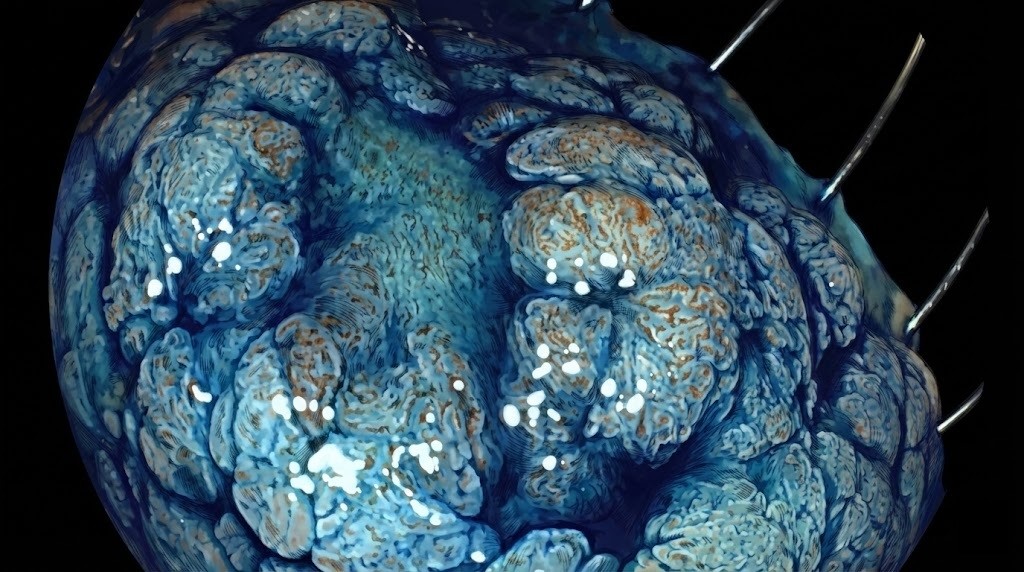

En el último congreso de la Sociedad Española de Endoscopia Digestiva (SEED), uno de los dos directores científicos de nuestro centro, el Dr. José Carlos Marín, fue invitado a un Live de Endoscopia. No era un caso especialmente fácil sino una lesión grande y complicada en el ciego, una zona especialmente delicada del colon por su pared fina y su localización. Cientos de especialistas siguieron paso a paso cómo se analizaba la lesión, qué criterios se usaban para escoger la técnica y cómo una resección endoscópica avanzada, bien planificada, podía evitar una cirugía de colon que, en algunos centros, habría sido la primera opción.

Este tipo de invitaciones no ocurren por casualidad; suelen reflejar la confianza de la comunidad científica en la experiencia con pólipos complejos y rescates endoscópicos. Y, sobre todo, dicen algo importante para los pacientes: en manos expertas, muchos pólipos grandes y difíciles pueden tratarse con una colonoscopia, sin abrir el abdomen ni quitar un segmento del colon.